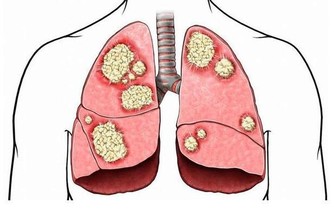

4. 呼吸短促

如果心臟和肺部由於血栓而受到壓迫,則可能會出現呼吸短促。如果同時還有上述關於血栓的其他症狀出現,說明事態比較緊急,必須立即解決。現在馬上看醫生,還有機會恢復健康。

5. 胸痛

當血栓到達肺部時,人們就會在胸部和身體兩側產生劇烈疼痛。這種疼痛非常劇烈,而且有灼燒感,身體這塊區域都很痛苦,感覺很沉重。

不明原因並且日漸加劇的咳嗽,也可能是血栓的跡象,表明血栓雖然較小,但已經在肺部形成。更嚴重的跡象包括咳血或產生含有血液的粘液。